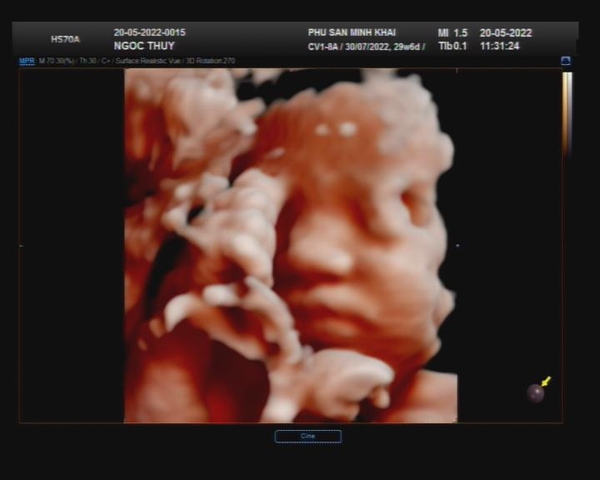

Siêu âm Chuyên khoa tại Phòng khám Phụ sản Minh Khai là dịch vụ tạo nên giá trị khác biệt. Khi bệnh nhân có dấu hiệu bất thường về các triệu chứng phụ khoa hay phụ nữa trong quá trình thai kỳ. Tại đây, đội ngũ y bác sĩ của chúng tôi sẽ thực hiện chuẩn đoán, và thưc hiện kiểm tra đúng kỹ thuật chuyên khoa bằng các loại siêu âm chuyên sâu như:

Chức năng Siêu âm chuyên khoa:

- Siêu âm sàng lọc Tim bẩm sinh cho thai và cho bé sau sinh